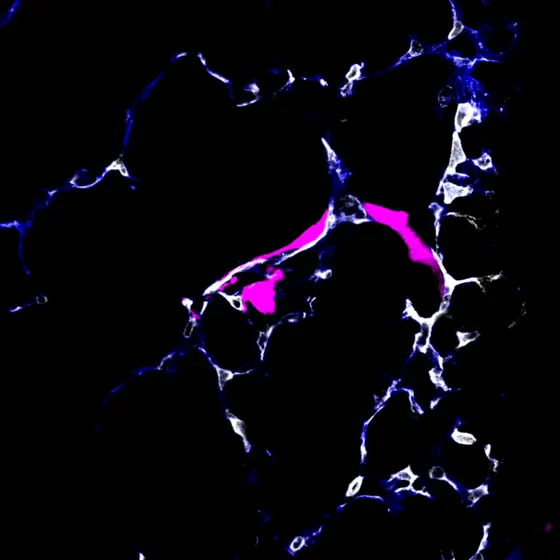

Partially extravasated metastasizing tumor cells (pink) exiting from the pulmonary circulation (white).

The team led by the two first authors Moritz Jakab and Ki Hong Lee discovered that some tumor cells, once they have arrived in the metastatic organ, leave the blood vessel and enter a resting state. Other cancer cells start to divide directly within the blood vessel and grow into metastases.

This delicate fate decision of the metastasizing tumor cells is controlled by the endothelial cells that line the inside of all blood vessels. They release factors from the Wnt signaling pathway that promote the exit of tumor cells from the blood vessel and thereby initiate latency. When the researchers switched off the Wnt factors, latency no longer occurred.

“At this point, we asked ourselves the question: Why do some cancer cells immediately form a metastasis, while others fall into a kind of sleep?“ says Moritz Jakab. The dormant and metastasizing cancer cells did not differ genetically, nor in many other molecular aspects. But the researchers were able to detect a subtle difference: The methylation of the DNA differed between the two cell types. Tumor cells, whose DNA was less methylated, responded sensitively to the Wnt factors, which resulted in extravasation from the blood vessel and subsequent latency. On the other hand, the more methylated cancer cells did not respond to the Wnt factors, remained in the blood vessel and immediately started metastatic growth.